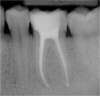

Exemple :

Une volumineuse carie s’est développée sur cette molaire inférieure. L’envahissement bactérien de la pulpe oblige le chirurgien-dentiste à nettoyer et désinfecter entièrement la cavité pulpaire (chambre pulpaire et canaux radiculaire), jusqu’aux extrémités des racines. Cet espace ainsi préparé est ensuite obturé de façon étanche (matériau blanc sur les radiographies).